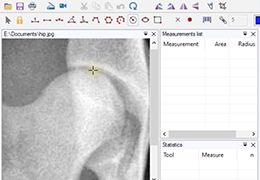

Multi-planar slicing.

Oblique slicing.

Window/level (brightness and contrast) presets.

Side-by-side comparative assessment for pre- and post-operative scans.